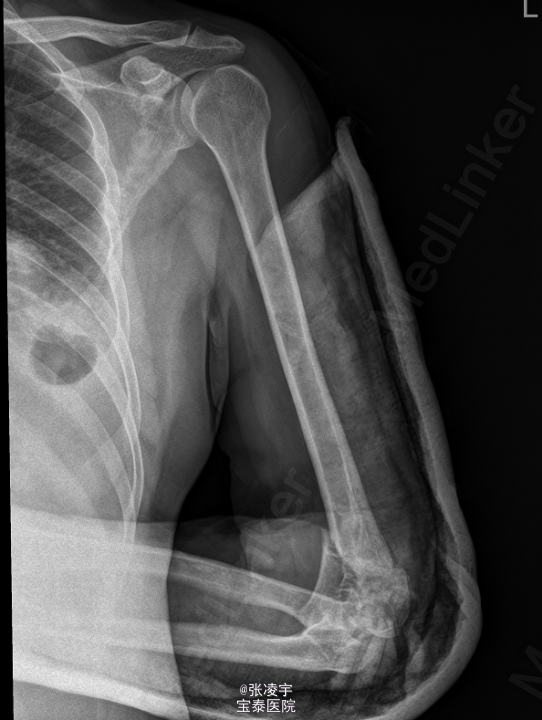

男,53岁,因“ 摔倒致双上肢疼痛5小时”于入院。 患者于5小时前从1米高处摔落,双上肢着地,伤后即感左右肘关节疼痛,伴左肘关节出血、鼻出血,至当地医院就诊。

右上肢伸直受限,感觉无异常,左上肢石膏敷料固定,未见明显渗血渗液,双下肢活动自如,肌力V级,病理征阴性。X线:左侧肱骨骨折。

初步诊断: 1.左肱骨开放性骨折,右肘关节脱位? 行左肘关节韧带修补外固定架固定 。